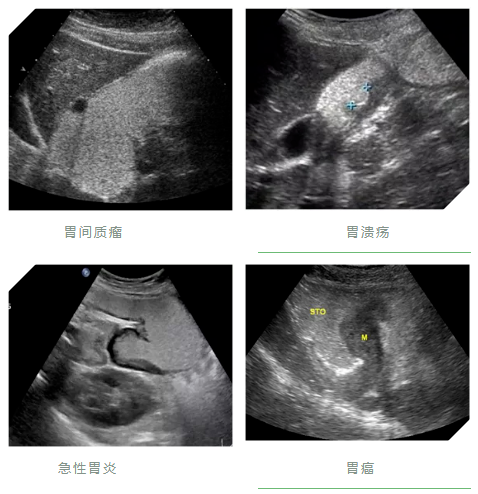

1.肿瘤性病变:胃癌、胃息肉,胃间质瘤,十二指肠肿瘤等图片为胃窦癌胃肠超声造影图像;

2.炎性与溃疡性病变:急、慢性胃炎,胃及十二指肠溃疡等;